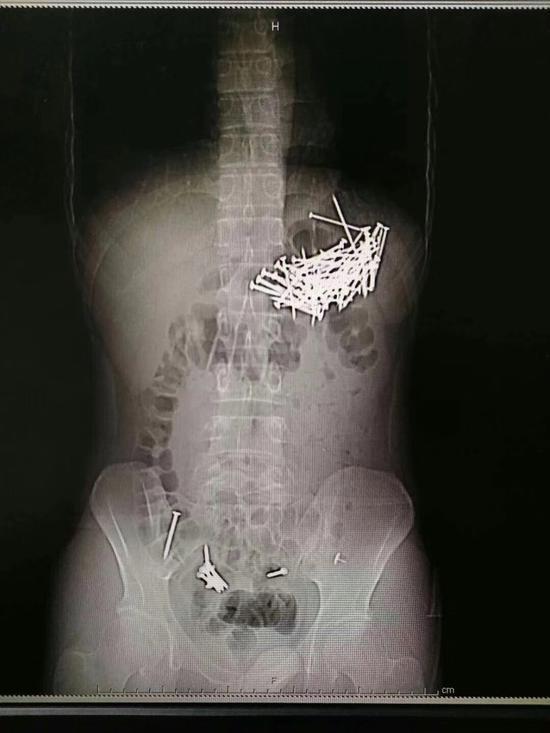

肚中取出87根鐵釘:2018年8月9日晚,郴州市第一人民醫院醫生從25歲的小伙唐某體內取出87根鐵釘。小伙吞鐵釘自殺,而且吞了87根鐵釘,醫生通過手術從他的肚中取出鐵釘,小伙獲救。

8月9日晚上7點左右,經過4個小時的忙碌,醫生從小伙子的腹腔和胃部等取出共87根鐵釘,每根釘子大約四五厘米長。

手術醫生胡志輝介紹,這個小伙子吞食了87根鐵釘和7枚圖釘,其中6枚圖釘被病人自行排出,目前余下一枚圖釘在直腸附近,由于體積較小,病人應該可以自行排出。